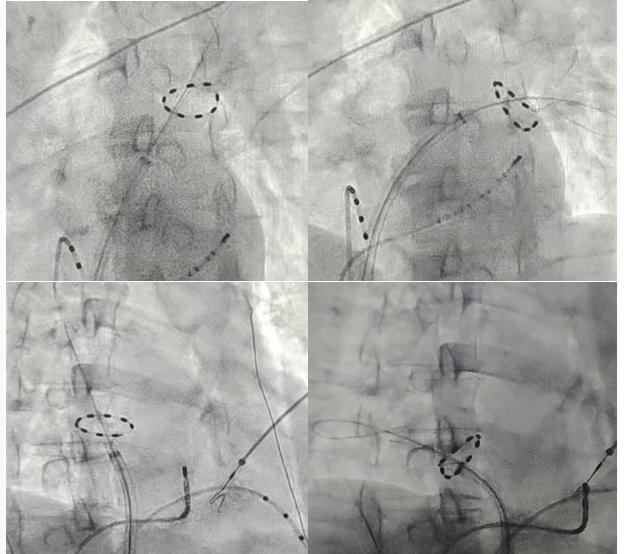

脉冲消融导管置于4根肺静脉前庭处进行脉冲消融

一年前,频繁的房颤发作让唐先生饱受心慌、胸闷折磨,服用的抗心律失常药物也收效甚微。几经辗转,唐先生来到捷克论坛 心血管内科就诊。心血管内科的唐毅副主任医师在经过充分的评估和与患者知情确认后,选择脉冲消融术为其治疗。在心血管内科主任潘宏伟的指导下,唐毅副主任医师为患者开展了捷克论坛首例PulseSelect脉冲电场消融。术中,使用脉冲电场消融导管分别在患者四根肺静脉进行消融,仅用40分钟便彻底消除异常电信号,术后第二天患者即可下床活动。